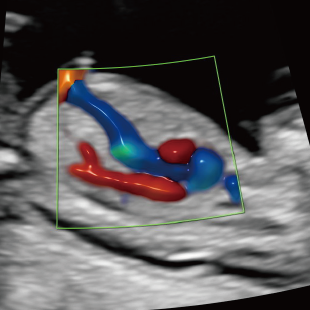

妊娠後期は、胎児の成長がさらに進み、発育の途中で現れてくる変化を確認できる時期です。中期の検査では問題が見られなかった場合でも、成長に伴って形態の変化が現れることがあります。また、構造だけではなく、胎児機能(赤ちゃんの元気度)の評価も可能となります。後期スクリーニングでは、各臓器の状態や構造に加え心臓の動きや血液の流れなどをより詳しく観察します。

胎児ドックの様子_後期_頭 胎児ドックの様子_後期_心臓 胎児ドックの様子_後期_心臓 胎児ドックの様子_後期_足 胎児ドックの様子_後期_4D